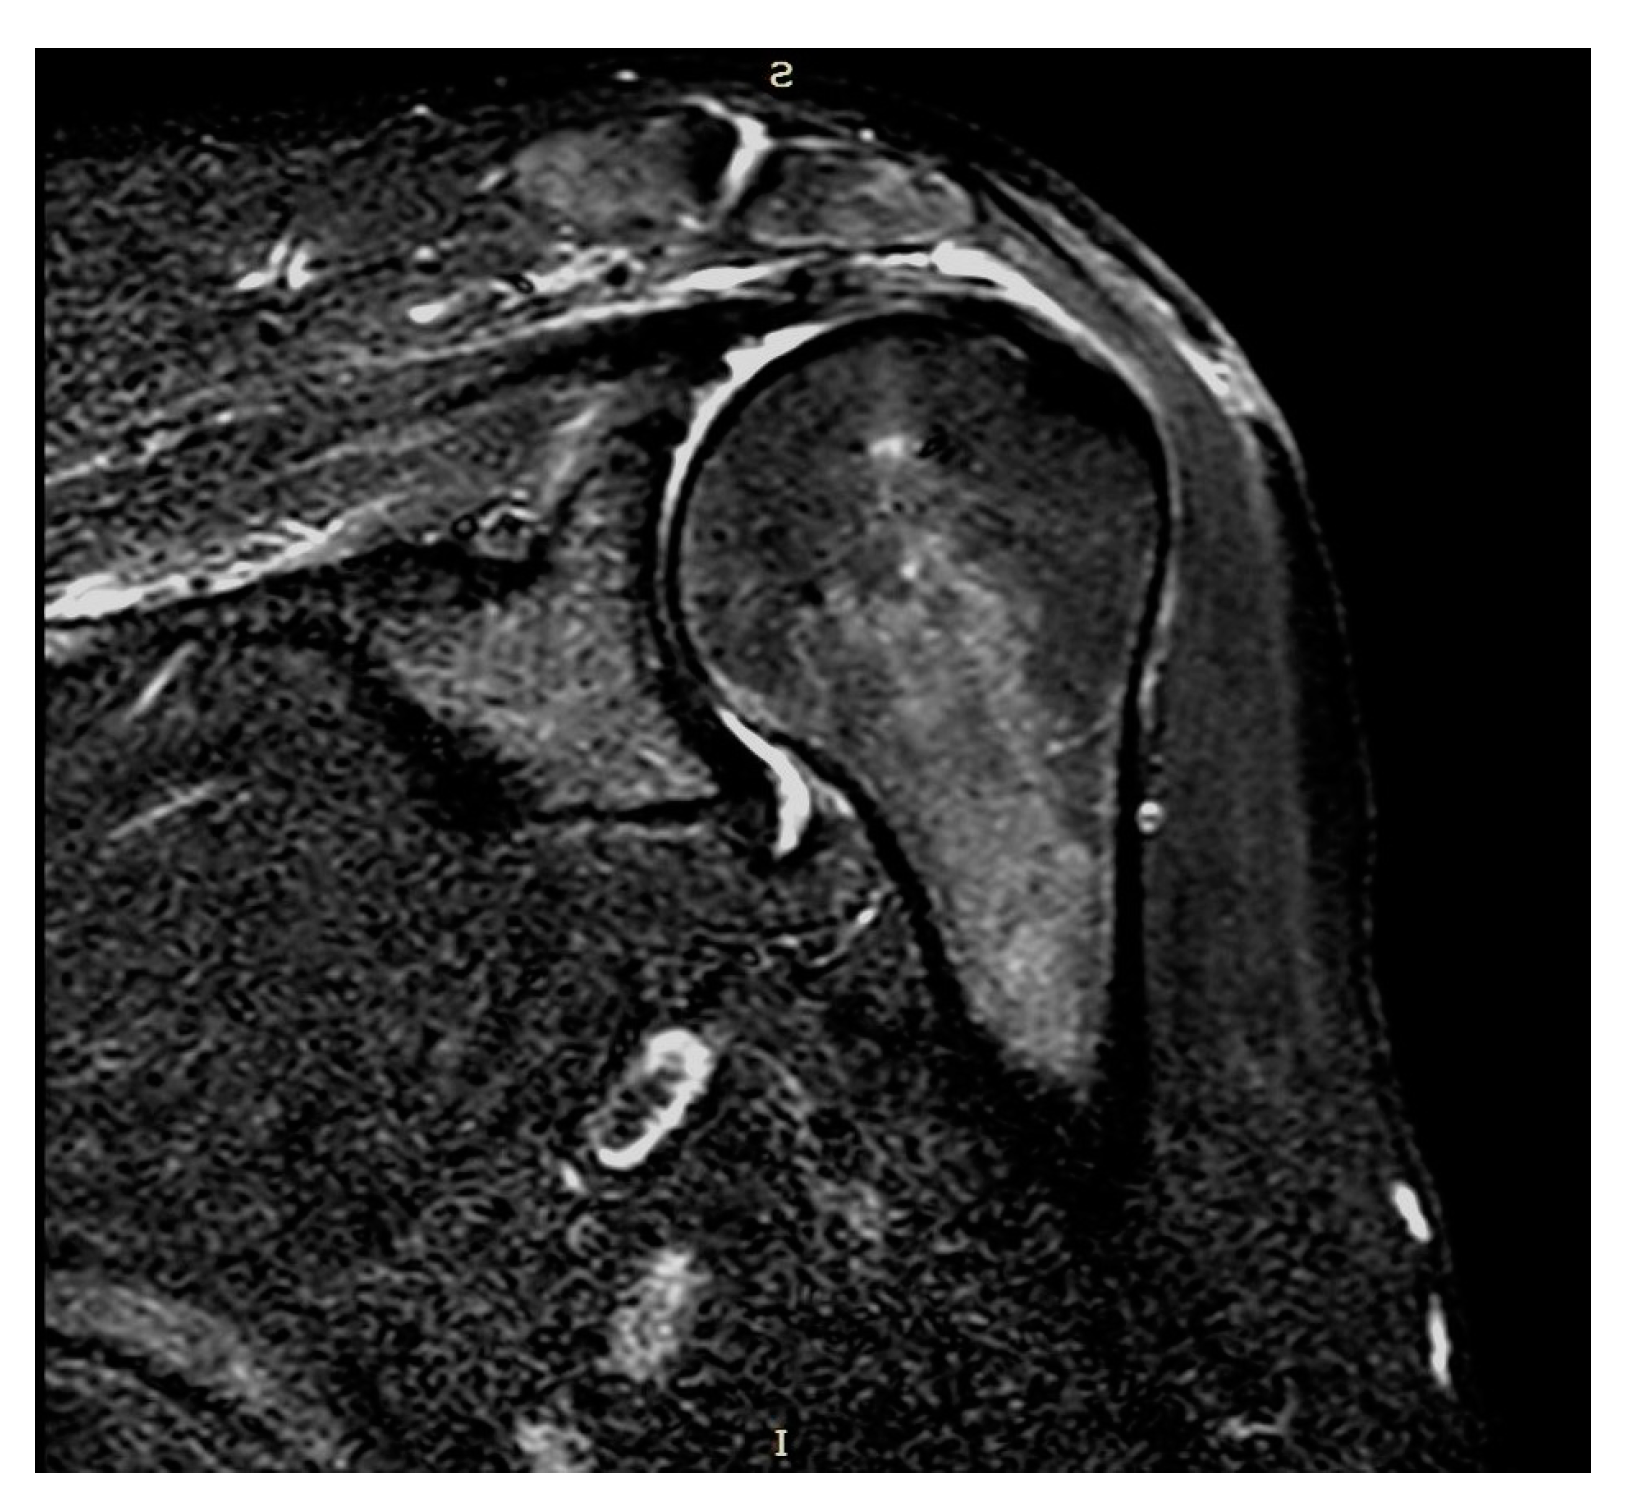

Plain radiographs and MRI showed coverage and centering of the humeral head, tendon continuity, and absence of fatty degeneration in all patients (Figure 3 and Figure 4).

Figure 4. Coronal STIR-weighted MRI.